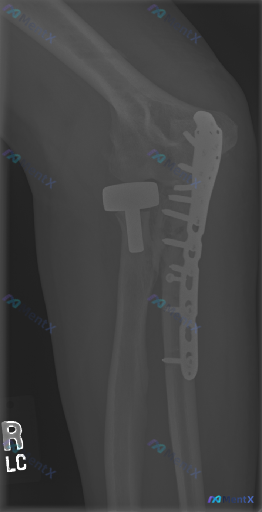

这张右肘X光片有“偏离正常”,是术后改变还是新问题?

整理了一份右肘关节侧位X光片的资料,标注是「OR 19 PORT」(术后便携片)。 影像里能看到: 1. 右肱骨远端有金属钢板和多枚螺钉固定 2. 有金属伪影遮挡了部分骨骼细节 3. 局部软组织密度看起来偏高 4. 关节对位整体还可以 问题是:影像里说有“偏离正常”,但结合术后背景,大家第一眼会怎么...

整理到一份右肘关节的术后复查影像资料,影像科的结论比较平稳,但仔细看分析过程,其实埋了几个雷。 先看核心影像表现: - 右肘做过两个手术:尺骨近端背侧锁定钢板(跨鹰嘴)+ 桡骨头金属假体置换 - 报告写“内固定物及假体在位,未见明确松动、断裂或再骨折” - 但也提了一句“常规脂肪垫征不易评估” 这份...